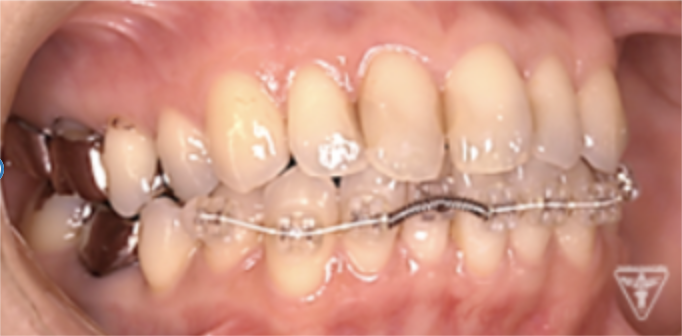

矯正治療

矯正治療による歯軸、叢生改善